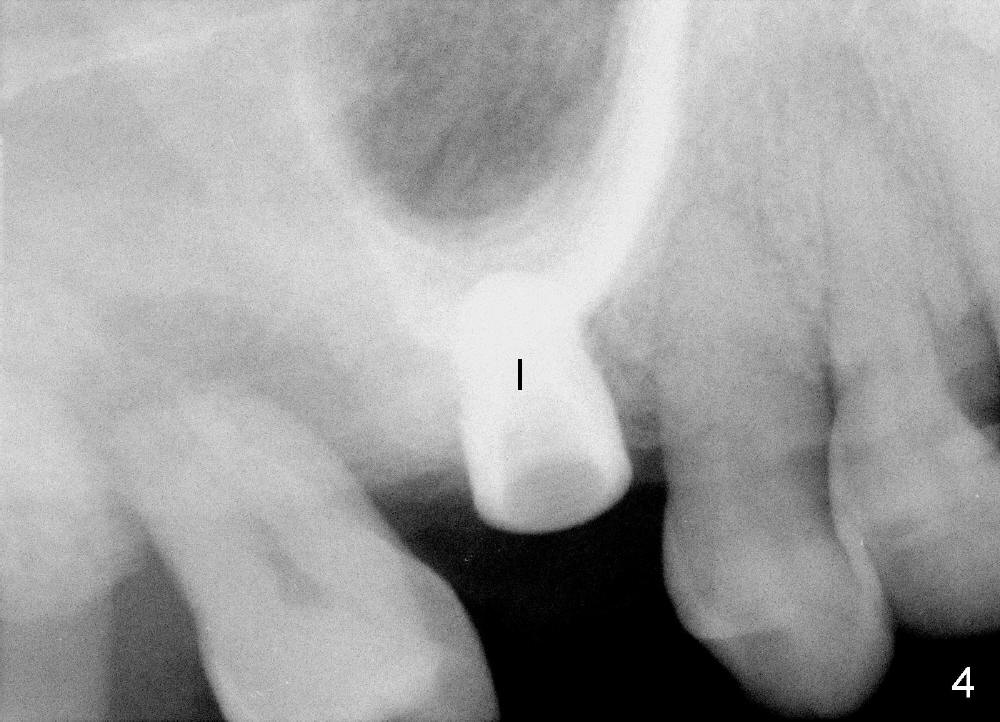

Bone expander kit is planned for for the case at the site of #3 with apparently normal buccolingual width (Fig.1). Bone density proves to be not low intraoperatively. First, when the 1.6 mm pilot drill is being used, the bone does not feel soft. Second, the first expander (2.6 mm, Fig.2 E) cannot be driven into the osteotomy (following the pilot drill) unless 2.5 mm reamer is used. Third, when larger expanders (until 3.8 mm) and 5x11 mm tap (Fig.3 T) are being used, the distobuccal plate starts to crack, although insertion torque of 5.3x8 mm implant is >50 Ncm (Fig.4). Using bone expanders is time consuming. In brief, when the buccolingual width is within normal limit and bone density is not low, traditional osteotomy should be adopted. It is better to use reamers to collect autogentous bone at the same time. The bone can be put back later into the osteotomy for sinus lift. Another drawback of this case is that the implant is not placed deep enough (Fig.5: 3 months postop). When a crown is cemented 1 year 4 months postop, the distal coronal portion of the implant is supragingival, although there is no infection.

Although the tooth #2 (Fig.4) needs extraction and immediate implant next time, the patient has lost #8 and 9 for long time. The bone also looks dense. Are we going to use bone expansion technique?